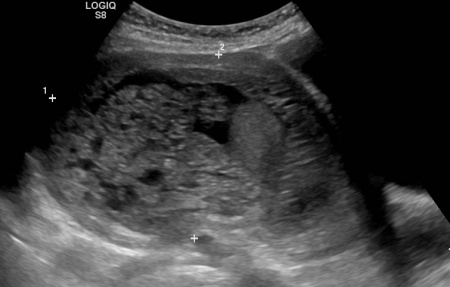

Molar Pregnancy - WikEM

Molar pregnancy - WikEM www.wikem.org

molar pregnancy ultrasound wikem transabdominal steadyhealth

molar pregnancy ultrasound snowstorm wikem findings